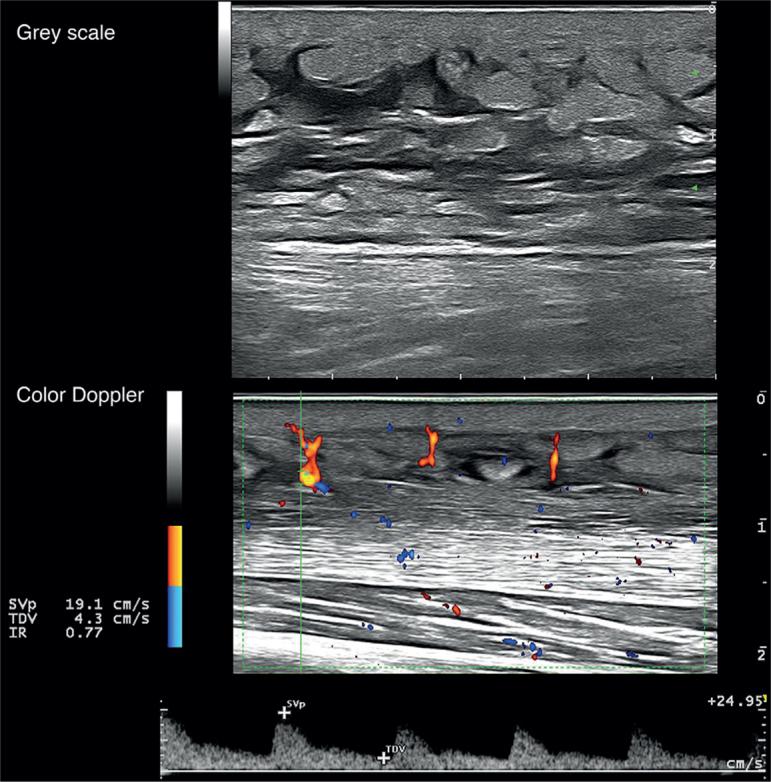

Sclerodermoid chronic graft-versus-host disease (scGVHD) is a severe complication of allogeneic haema-- topoietic stem cell transplantation. The aim of this study was to investigate the usefulness of high-frequency ultrasound of the skin in assessing the inflammatory patterns and prognosis of patients with scGVHD. A prospective study was carried out with patients who developed scGVHD in the period June 2016 to April 2018. Clinical and ultrasound examinations were performed on the first visit and at 6-month follow-up. A total of 24 patients were included in the study. A 6-month follow-up high-frequency ultrasound of the skin was performed on 20 of the 24 patients. Abnormal B-mode findings in high-frequency ultrasound of the skin consisted of hypoechogenic dermis, hypoechogenicity of septa and hyperechogenicity of lobules in hypodermis. No differences were observed in these basal parameters between treatment progressive/non-responding and inactive/responding scGVHD groups of patients. Basal Doppler showing increased vascular flow with a systolic peak ≥10 cm/s and a vascular resistance index ≥ 0.70 was observed only in those patients who developed progressive/non-responding scGVHD (62.5% vs 0% p = 0.006). In conclusion, Doppler ultrasound is a useful tool to assess the inflammatory activity and outcome of scGVHD. These findings could enhance patient management and help to guide treatment decisions.

硬皮病样慢性移植物抗宿主病(scGVHD)是异基因造血干细胞移植的一种严重并发症。本研究的目的是探讨皮肤高频超声在评估scGVHD患者炎症模式和预后方面的作用。对2016年6月至2018年4月期间发生scGVHD的患者进行了一项前瞻性研究。在首次就诊时和6个月随访时进行临床和超声检查。共有24例患者纳入研究。24例患者中的20例进行了6个月随访的皮肤高频超声检查。皮肤高频超声的异常B超表现包括真皮低回声、间隔低回声和皮下小叶高回声。在治疗进展/无反应组和无活动/有反应组的scGVHD患者之间,这些基础参数未观察到差异。仅在发生进展/无反应性scGVHD的患者中观察到基础多普勒显示血管血流增加,收缩期峰值≥10 cm/s,血管阻力指数≥0.70(62.5%对0%,p = 0.006)。总之,多普勒超声是评估scGVHD炎症活动和预后的有用工具。这些发现可加强患者管理并有助于指导治疗决策。